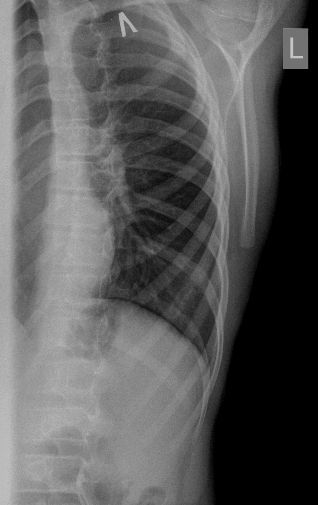

После УЗИ - сделал рентген, изменения в ребре есть, но в глаза не бросаются

Diagnosis of Ewing's Sarcoma is suspected

Выставил диагноз саркомы Юинга с MTS.Ребёнок поехал в РНПЦ онкологии, я думаю там и будет лечиться дальше. Но хотелось бы узнать мнение общества, насколько я прав? Заранее благодарен :)